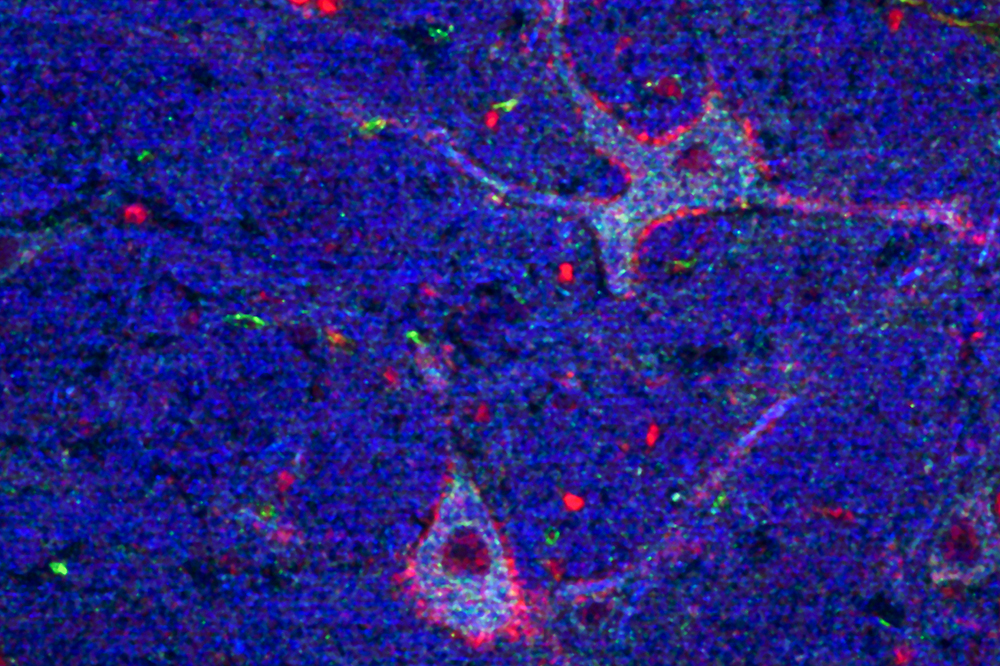

Researchers believe that large cells called nucleus gigantocellularis neurons, pictured here, modulate blood flow by releasing nitric oxide.

In her work, using mice, Tabansky focused on a subtype of extremely large neurons in the NGC with links to virtually the entire nervous system, including the thalamus, where neurons can activate the entire cerebral cortex. “If you just look at the morphology of NGC neurons, you know they’re important,” Pfaff says. “It’s just a question of what they’re important for. I think they’re essential for the initiation of any behavior.”

To Tabansky’s surprise, the NGC neurons were found to express the gene for an enzyme, endothelial nitric oxide synthase (eNOS), which produces nitric oxide, which in turn relaxes blood vessels, increasing the flow of oxygenated blood to tissue. (No other neurons in the brain are known to produce eNOS.) They also discovered that the eNOS-expressing NGC neurons are located close to blood vessels.

In Pfaff’s view, the neurons are so critical for the normal functions of the central nervous system that they have evolved the ability to control their own blood supply directly. ‘“We’re pretty sure that if these neurons need more oxygen and glucose, they will release nitric oxide into these nearby blood vessels in order to get it,” he says.